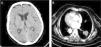

We report the case of a 71-year-old woman, non-smoker, with situs inversus totalis who was admitted to a neurology department due to a 2-month history of progressive visual and hearing loss. Physical examination showed bilateral amaurosis and hypoacusia. Brain computed tomography (CT) showed no intracranial lesions (Fig. 1A) and gadolinium-enhanced magnetic resonance imaging (MRI) of the brain showed no focal or diffuse leptomeningeal enhancement or tumoral lesions. A lumbar puncture was performed and pathological analysis of the cerebrospinal fluid (CSF) revealed adenocarcinoma cells with immunohistochemistry showing positivity for TTF-1 and cytokeratin 7, indicative of a pulmonary origin. A chest CT showed a 3cm lobulated mass in the right lower lobe (RLL) (Fig. 1B). A percutaneous CT-guided core biopsy was conducted in an attempt to obtain additional tumor tissue to perform EGFR mutation sequencing. Histology showed pulmonary parenchyma occupied by neoplastic structures with adenocarcinoma features which stained diffusely for TTF-1 and cytokeratin 7. The patient died during hospital admission due to aspiration pneumonia. One week later the biopsy of the RLL mass showed that the tumor harbored EGFR G719C mutation in exon 18.